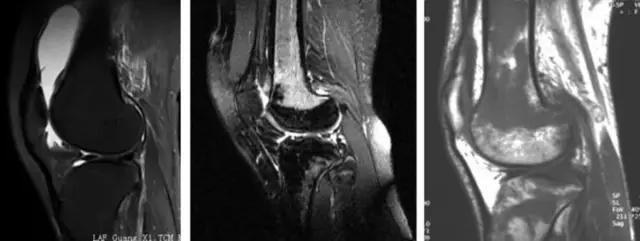

利用相关原理——

地中海贫血与白血病均为血液系统的问题,主要表现在骨髓,疾病的发病机理有别,MRI表现也不相同;我们可能不是很熟悉这些疾病,也能够从MRI发现区别。图1:正常膝关节 图2:地中海贫血 图3:白血病